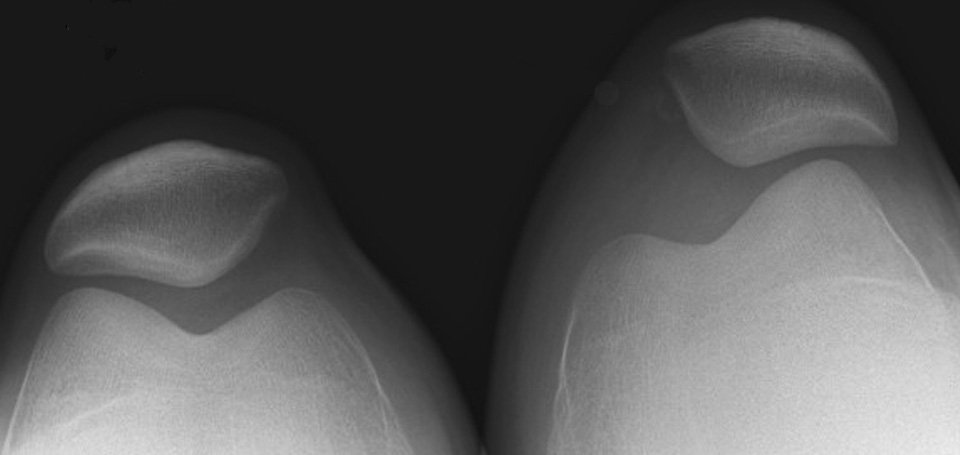

تشخيص الخلع الرضفي

عادًة ما يكفي الكشف على المريض للوصول للتشخيص، حيث يجد الطبيب المعالج أنه يمكنه تحريك الصابونة بسهولة للجهة الخارجية للركبة. ولكن قد يتم عمل أشعة للتأكد من موضع الصابونة بالنسبة لعظمة الفخذ، وكذلك للتأكد من عدم وجود كسور مصاحبة للخلع.